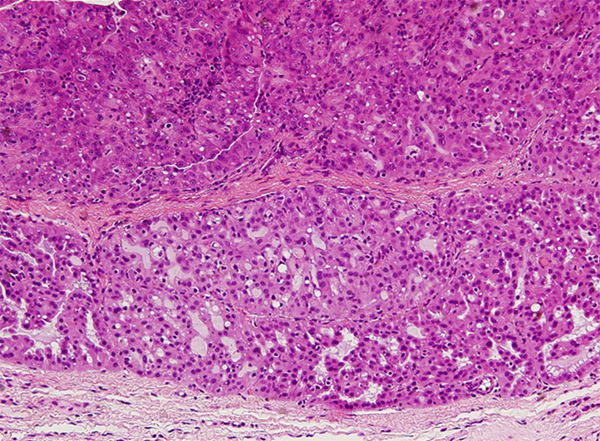

下顎の臼歯部にできた3mmほどの小腫瘤

病理組織学的;腺癌